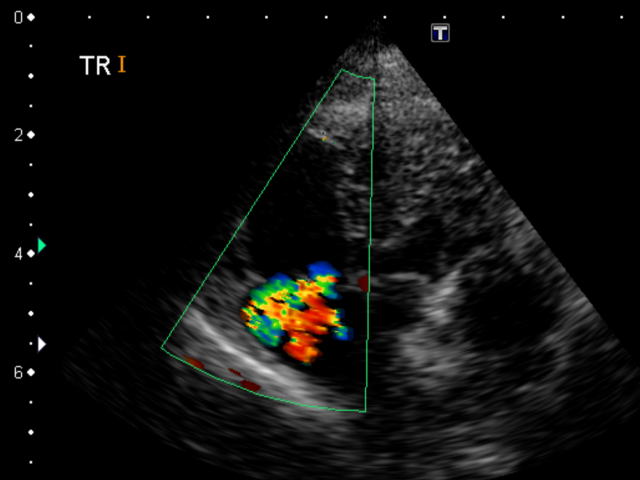

確定診断は右心カテーテル検査による、肺動脈圧の測定が必要ですが、通常は心臓エコー検査で三尖弁(右心房と右心室の間の弁)の逆流速度から、肺動脈圧を推定します。

(モザイク状のカラーになっている部分が、三尖弁の逆流)